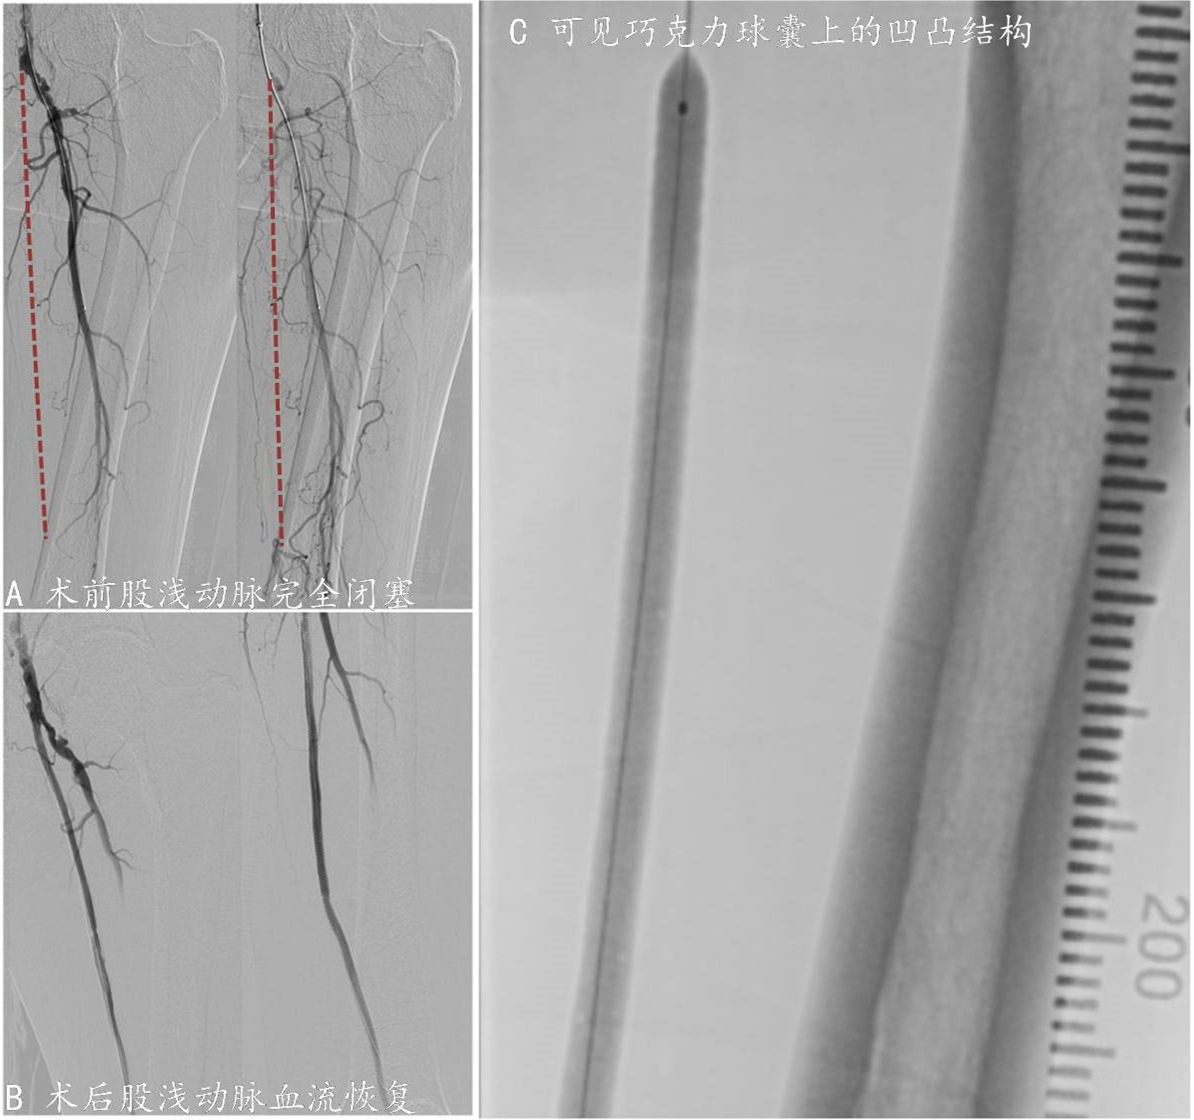

林先生,65岁,长期间歇性跛行,行走50余米后即左下肢疼痛、无力、无法行走,休息数分钟后缓解,继续行走50米上述症状再次出现。在张童医师门诊完善左下肢踝肱指数检查,ABI只有0.6。术中造影见左侧股浅动脉自起始段到远端完全闭塞,下肢血液供应依赖侧枝循环。张童医师以丰富经验顺血流方向通过病变后,采用6mm直径巧克力球囊进行血管准备,获得满意血流后铺设支架维持通路、应用药物涂层球囊抑制内膜增生、再狭窄闭塞。术后林先生左下肢ABI恢复至0.9,术后1天便健步如飞,在病房走500米都非常轻松。

图3 巧克力球囊用于股浅动脉完全闭塞病变血管准备

A术前股浅动脉完全闭塞

B术后股浅动脉血流恢复

C可见巧克力球囊上的凹凸结构